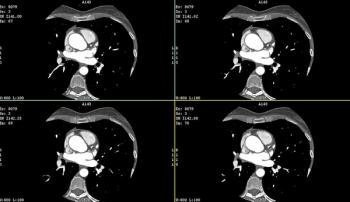

For myocardial extracellular volume quantification, single-phase and dual-phase photon-counting CT provided over 20 percent higher correlation with cardiac MRI in contrast to dual-phase energy-integrating detector CT, according to new research findings.

For pediatric patients with congenital heart disease, new research showed that cardiac PCCT yielded comparable signal-to-noise and contrast-to-noise ratios to energy-integrating detector CT at over a 43 percent lower dose length product.